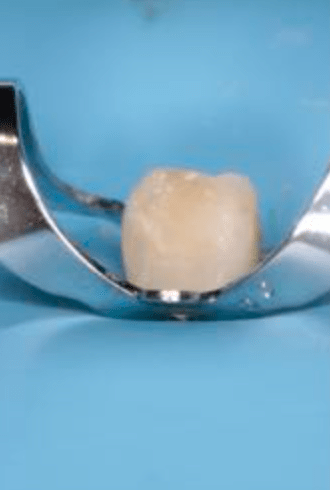

Reconstrucción preendodóntica

Molar superior

Reco palatina

Reco pared vesticular

Reco pre-endo gingivectomái, pared yuxtaosea

Reco pre-endo, molar inferior

Reco preendo + 4 conductos molar superior

Reco preendo + gingivectomía

Reco preendo, 2o Molar superior

Reconstrucción debajo de puente